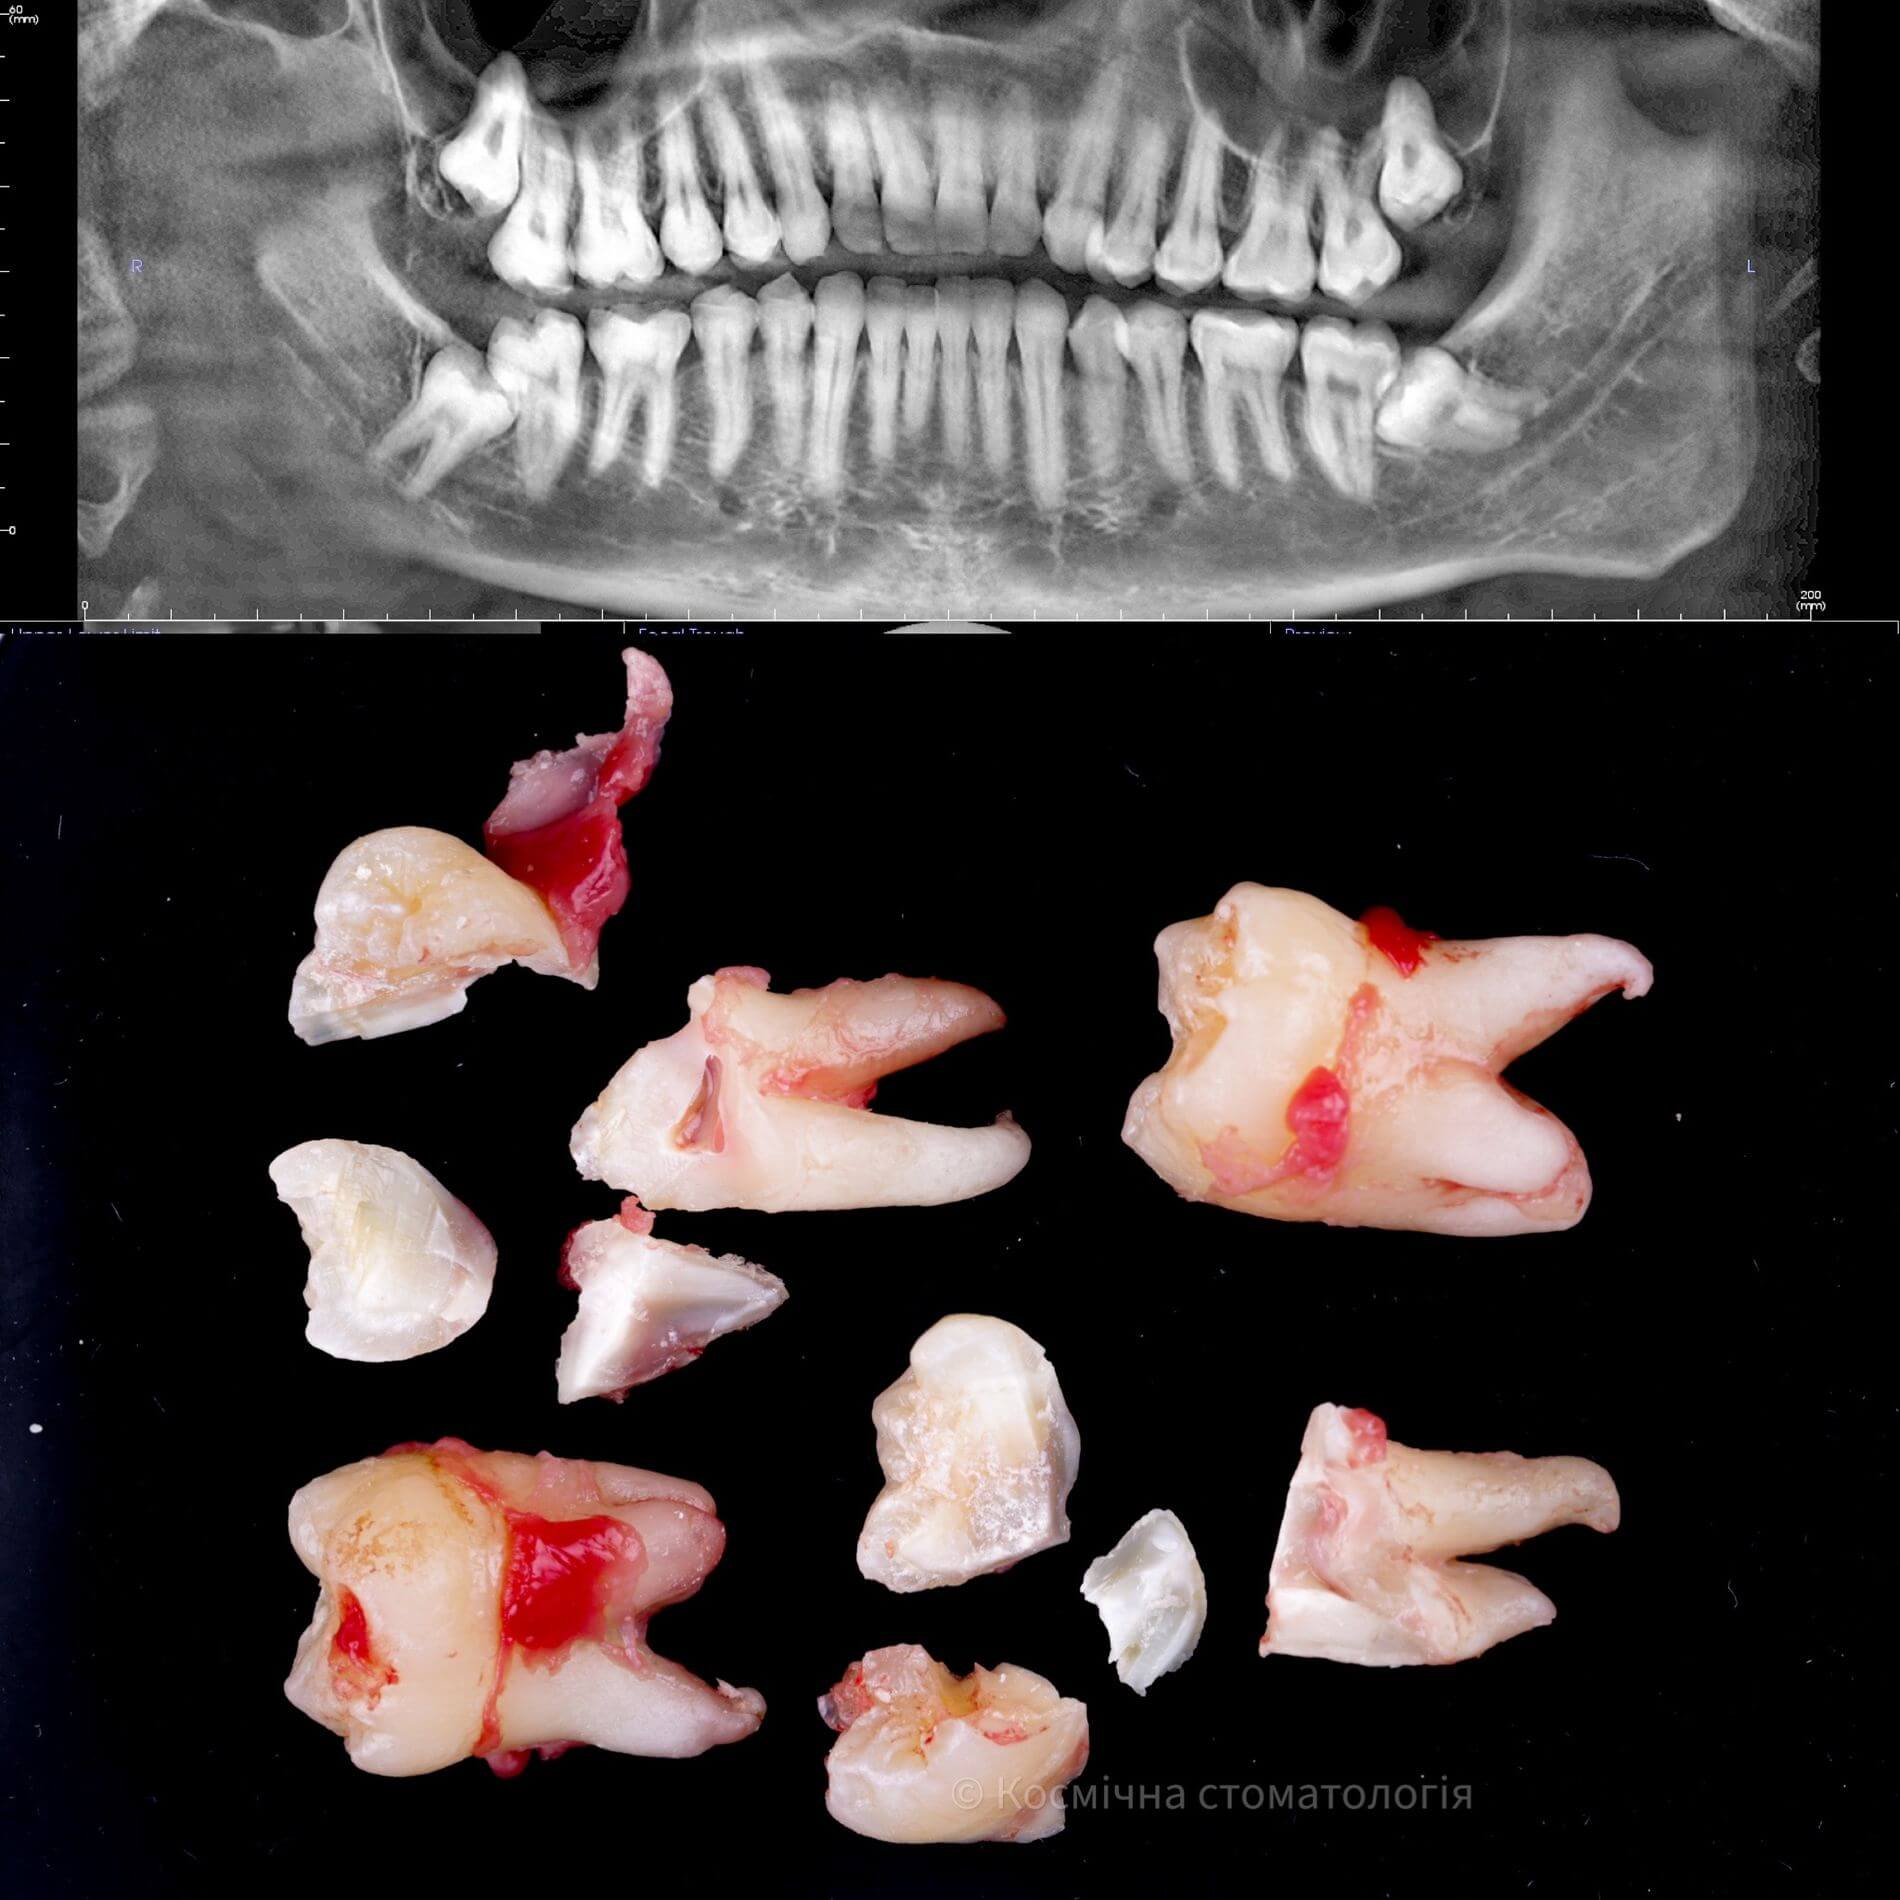

• Полное удаление зуба - если зуб полностью прорезался и имеет сросшиеся корни.

• Отдельное удаление коронки зуба и его корней - если зуб прорезан и корни растут по отдельности.

• Удаление зуба по схеме 1 или 2 с разрезом десен - если зуб прорезан частично.

• Разрез десен, освобождение зуба от близлежащей кости ультразвуком и удаление по схеме 1 или 2 - если зуб не прорезался, но беспокоит.

Галерея